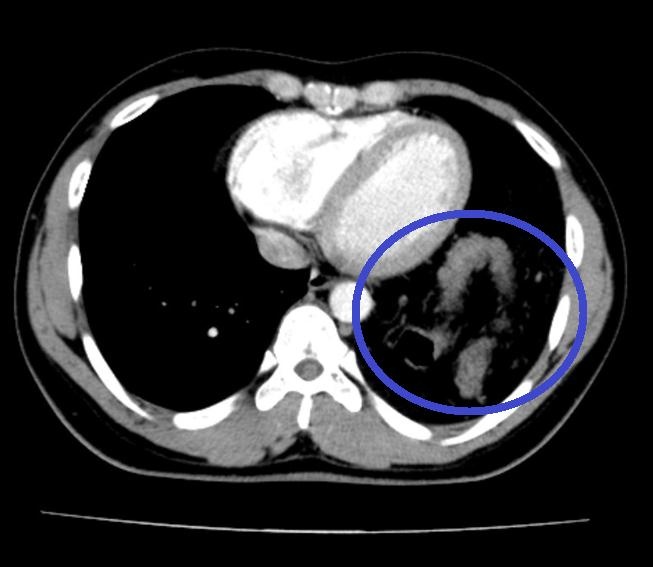

Đại tràng nằm trong ngực trái trên cắt lớp vi tính ngực của nam bệnh nhân. Ảnh: BVCC.

Tại đây, bệnh nhân H. được chỉ định mổ nội soi để sửa tổn thương và phục hồi cơ hoành. Khi đưa máy soi vào ổ bụng, phẫu thuật viên nhận thấy gần toàn bộ đại tràng ngang, lách, dạ dày và mạc nối lớn đã chui qua cơ hoành lên khoang màng phổi bên trái. Sau khi đưa các tạng trên trở lại ổ bụng, tổn thương cơ hoành bên trái lộ rõ là một lỗ khuyết rộng khoảng 6x8 cm.

- Cắt lớp vi tính và cộng hưởng từ: Thấy vị trí gián đoạn của cơ hoành, hình ảnh các tạng thoát vị, giúp đánh giá được thể bệnh và đưa ra phương án điều trị phù hợp.